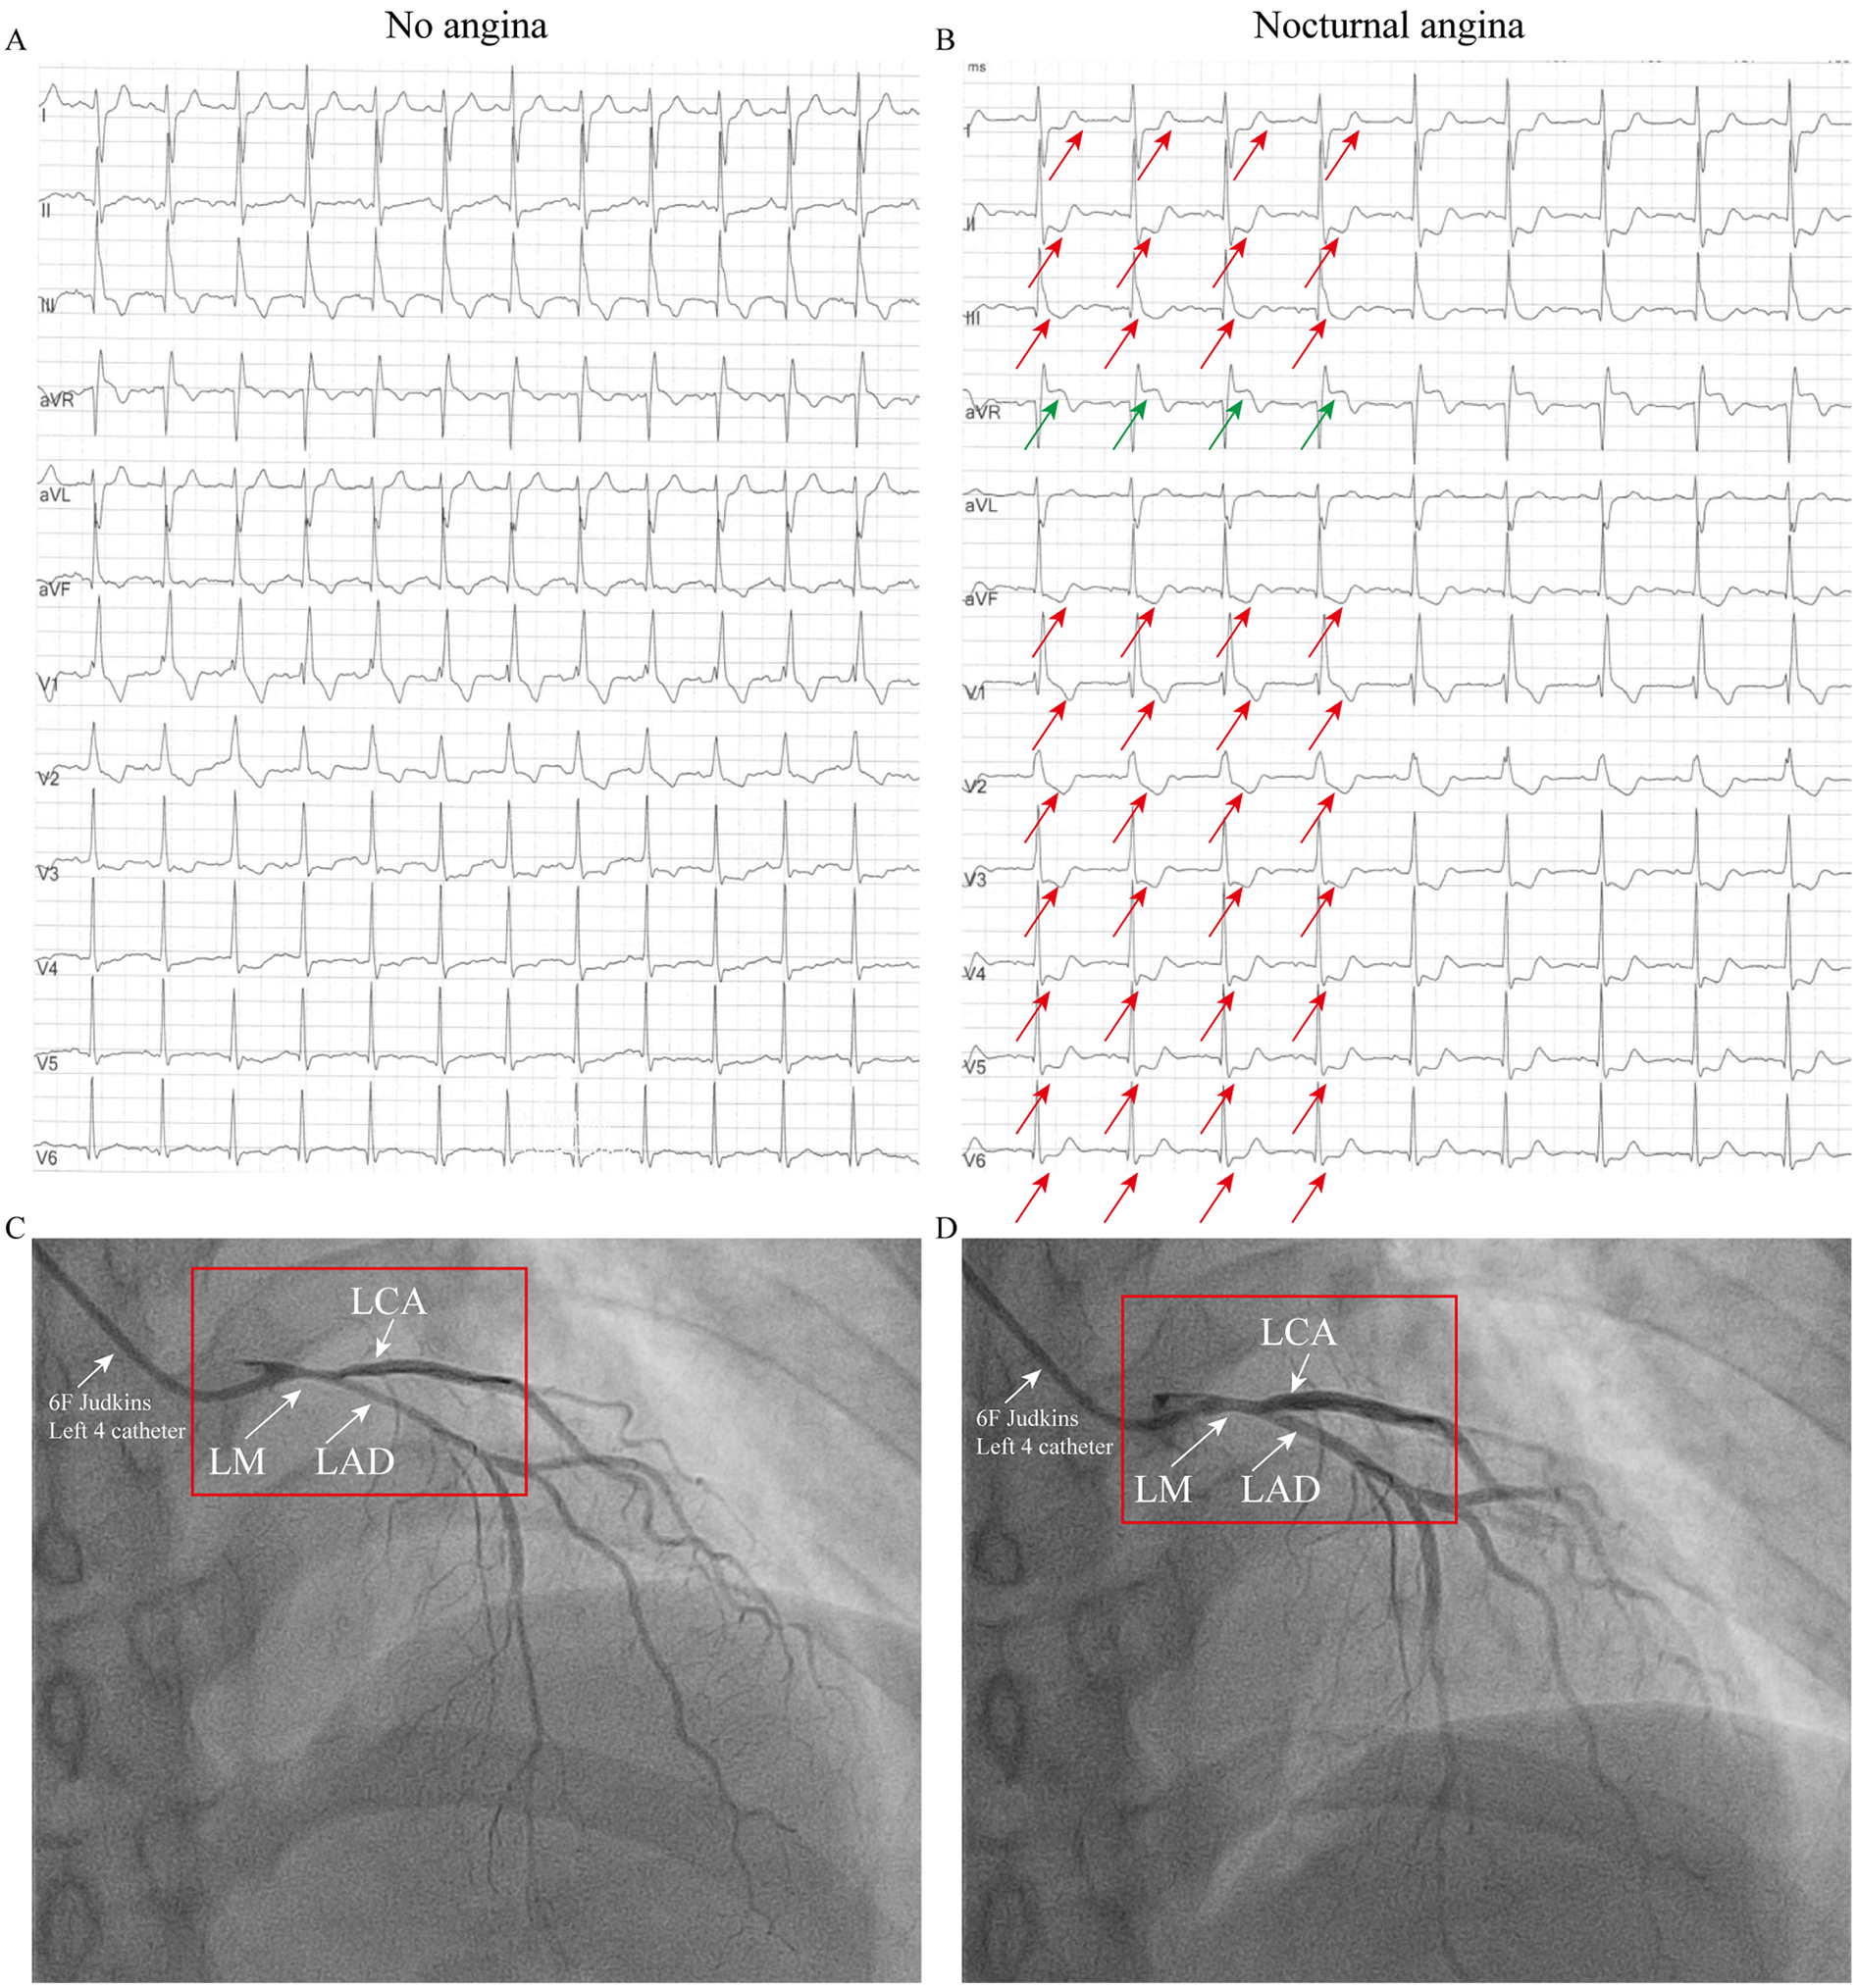

Figure 2

ECG and coronary angiography findings of case 2: (A) ECG during an asymptomatic period, showing a right bundle branch block (RBBB), T-wave inversions in leads III and aVF, and mild ST-segment depression in leads V3–V4. (B) ECG during chest pain showing acute ischemic changes: ST-elevation in aVR with diffuse ST-depression (I, II, V3–V6) and T-wave pseudonormalization in lead III (indicated by the arrow). (C) When the 6F catheter was inserted, about 60% spasm was observed in the left main coronary artery, the left circumflex artery and the left anterior descending artery (indicated by arrows). (D) Administration of 200 µg intracoronary nitroglycerin relieved the vasospasm (indicated by the arrow).

Patient 2 (Older Sister): The patient's identical twin sister had been treated at another institution in 2023 for a three-year history of chest pain, occurring predominantly at night and often persisting for 10 min. She also had no conventional risk factors for coronary artery disease (Supplementary Table 1). When the patient was not experiencing chest pain, the ECG was essentially normal, showing a right bundle branch block (RBBB), T-wave inversion in lead III, aVF and mild ST-segment depression in lead V3–V4 (Figure 2A). During symptomatic episodes, ambulatory ECG monitoring captured significant ST-segment elevation in lead aVR, and marked ST depression in lead I, II, V3–V6 and T-wave pseudonormalization in lead III during symptomatic episodes (Figure 2B). Coronary angiography demonstrated approximately 60% spasm in left main coronary artery, left circumflex branch artery and left anterior descending artery (Figure 2C) and a normal right coronary artery. Administration of 200 µg intracoronary nitroglycerin successfully relieved the vasospasm (Figure 2D). She was likewise managed effectively with calcium channel blockers and discharged symptom-free.